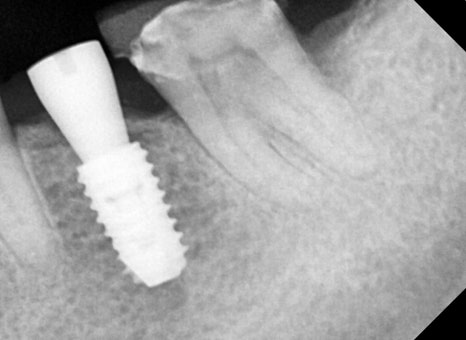

🖼️ 치료 전 사진

오른 사진: 신경치료 전, 기존 크라운(씌운 치아)을 제거하고 촬영한 부분 엑스레이입니다.

➡ 오래된 보철물 안쪽으로 충치가 깊게 생겨, 신경치료가 꼭 필요한 상태였습니다.

➡ 통증과 불편감이 있었고, 신경치료와 함께 앞쪽 빠진 치아 부위는 임플란트를 통해 기능 회복도 함께 진행했습니다.